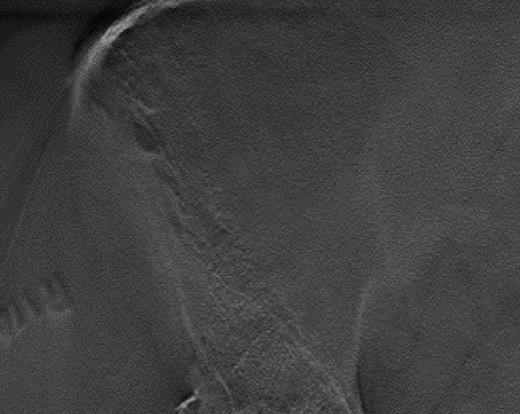

Sample lytic lesions on DT: